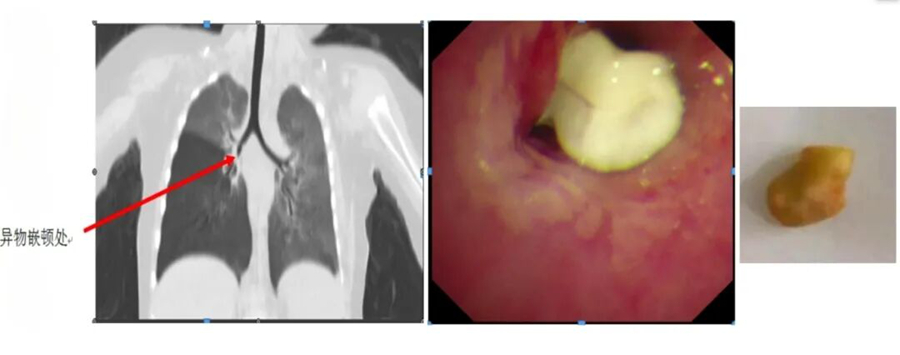

有一名患兒反復(fù)“肺炎”半年多,在當(dāng)?shù)蒯t(yī)院多次治療仍不見好轉(zhuǎn),家長慕名找到王文棣。她仔細(xì)為患兒聽診,敏銳地捕捉到孩子雙肺呼吸音左右不對(duì)稱這一關(guān)鍵線索,通過電子纖維支氣管鏡檢查揪出了“真兇”,竟是半粒花生米堵在了患兒的右主支氣管管口。當(dāng)異物被成功取出后,孩子的 “肺炎”再也沒有復(fù)發(fā)。